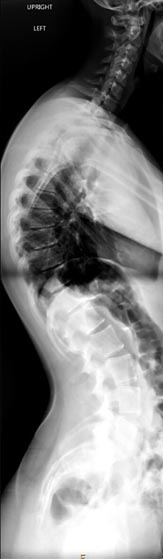

46 year old woman who previously had Harrington rod spinal fusion from T4 to L3 for idiopathic adolescent scoliosis who presents with back pain and left leg weakness from severe lumbar stenosis distal to her previous fusion.

3 months postop, patient is pain free and weakness completely resolved. She is able to stand upright without pain and improved posture.